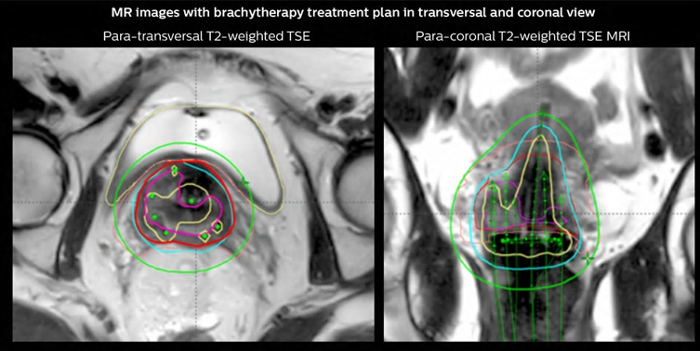

Cervical cancer treatment with 3D MRI-guided brachytherapy

Arhus University Hospital at the forefront of MRI guidance in adaptive cervical cancer radiotherapy.